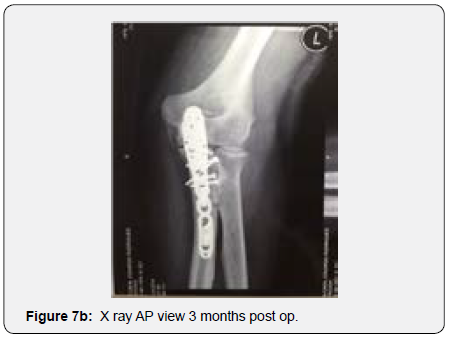

The remaining part of the bone graft was used in the non articular radial sided metaphyseal defect. The wound was then thoroughly irrigated and closed. The Patient was held in a cast for 2 weeks for soft tissue protection and from the 2nd to the 3rd Week he started passive range of motion exercises. After the 3rd Post operative week, the patient enrolled a physical therapy rehabilitation program, not directly controlled by the surgeon. At 3 Months post op the patient had regained adequate range of motion (flexion 120, extension15º, prono supination 90-0- 90º) and the x ray showed a stable elbow with graft integration and greater sigmoid notch articular congruence despite some heterotopic bone ossification/calcification in the olecranon fossa that might preclude full extension (Figures 7a & 7b). The Patient returned to his work 5 Months after surgery. At 3 Years post op he has no pain and has a ROM (Flexion 140º, extension-15º, prono supination 90-0-90) that allows him to do all of his daily living activities (Figures 8a & 8b). His CT Scan shows the healed bone graft and adequate ulno-humeral congruency (Figures 9a & 9b), Despite some degenerative changes are evident. He achieved a Mayo Elbow Performance Score (7) of 100.